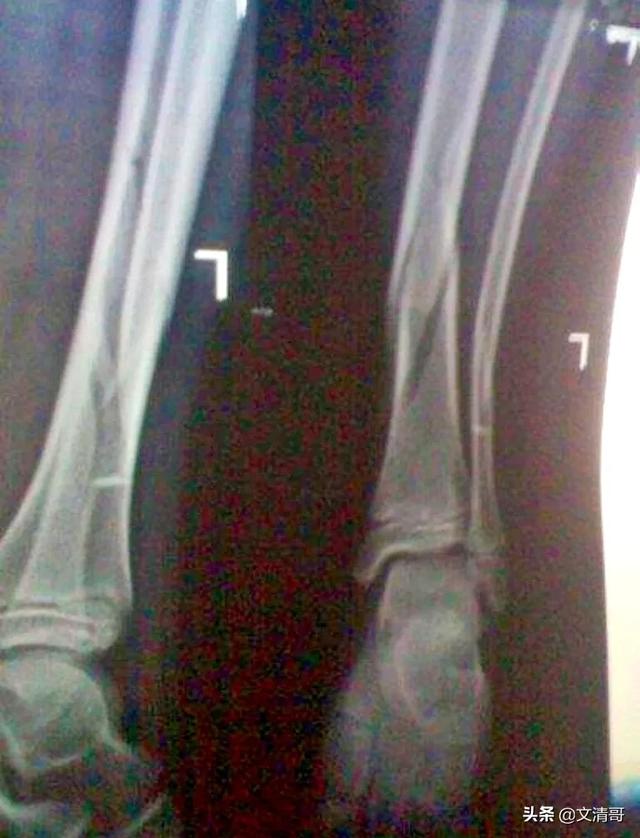

整形外科で起こりがちなもうひとつの事故は、次のようなものである。脂肪塞栓症..簡単に言えば、脂肪細胞が破裂して脂肪滴が放出され、この脂肪滴が脂肪細胞から放出される。脂滴血液循環にいくつかの小さな血管を通って、それは脂肪塞栓症を引き起こす可能性があり、血液中に脂質滴の少量は、あまりにも多くの問題を引き起こすことはありませんが、脂質滴の数が多い場合は、例えば、約9〜20グラムに達し、一度に肺循環その結果、肺循環域の約75%が閉塞し、患者は窒息と急性心不全を起こし、死に至る可能性がある。

この脂肪塞栓症は、骨折時にできることもあれば、手術中の事故によって起こることもある。

昔、ある若い男がいた。大腿骨ステムの粉砕骨折この患者は、入院して術前準備をした後、手術予定日の前日に、気分が急変し、著しくいらいらした。脂肪塞栓症症状が引き金となり、この患者は結局蘇生されなかった......。

- 脂肪塞栓症 脂肪塞栓症は、外傷後や整形外科手術後の重篤な合併症である。この病気の最も一般的な原因は、脂肪分が多いことである。大腿骨骨折などの長管骨の骨折.これは、局所的な損傷破裂後に骨や軟部組織の脂肪から脂肪細胞が遊離し、脂肪滴が静脈血流に浸入することによるもので、臓器や組織への脂肪塞栓症は主に肺血管系や脳血管系で起こる。外傷や骨折の3~72時間後に発生し、周術期にも起こりうる。